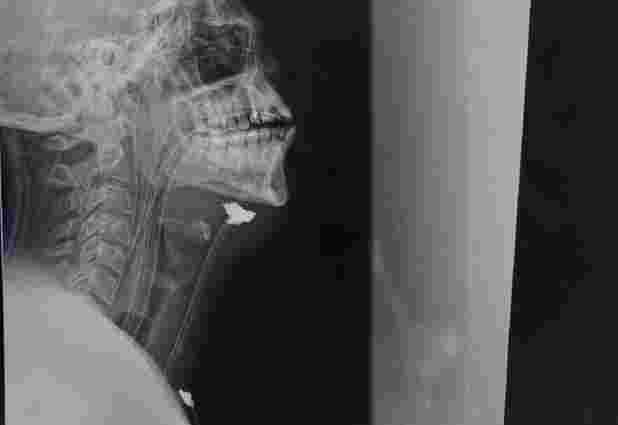

До прифронтового шпиталю захисника доставили у критичному стані, тиск уже не визначався. Йому провели реанімаційні заходи і після стабілізації стану терміново провели обстеження: рентген голови, шиї та грудної клітки, УЗД сонних артерій.

«Після обстежень пацієнту поставили діагноз: вогнепально-осколкове сліпе поранення. Уламок виявили в проекції судинного пучка, гематому та ознаки травми сонної артерії справа. Іншими словами, уламок снаряду потрапив у плече, пройшов через усю шию, розірвав сонну артерію і зупинився під щелепою», – повідомив ZAXID.NET судинний хірург, який вже тривалий час рятує бійців на сході країни, Тарас Кобза.